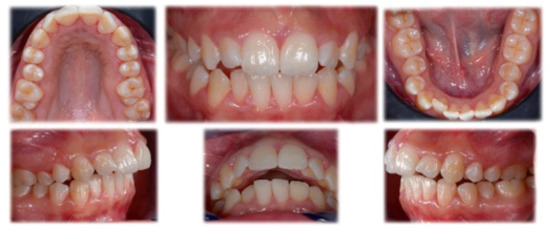

2.1. Diagnosis and Treatment Plan